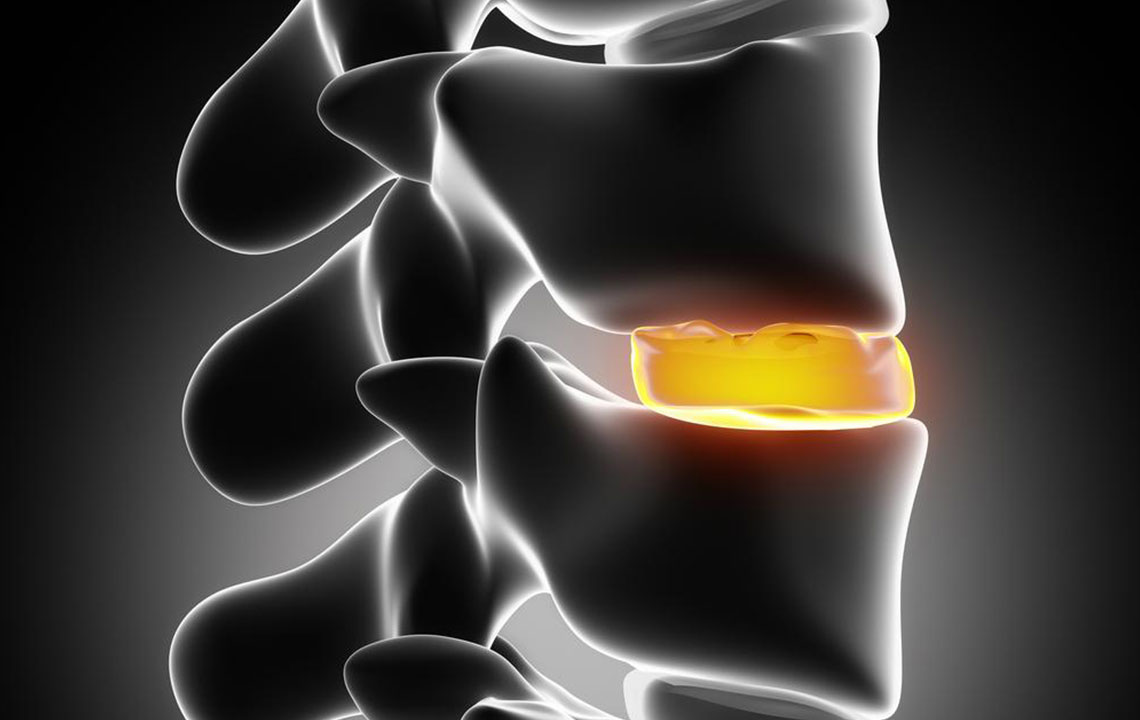

The spinal disc is the natural cushion that helps you absorb the shock of the glycoprotein and fibrocartilage that separate your vertebral bodies. They help you to have a normal movement at each level of spinal motion. Annulus forms the outer section of the spinal disc that consists of various layers of multi-directional fibrocartilaginous fibers. These fibrocartilaginous fibers are densely packed around the glycoprotein filled disc nucleus.

The injuries that incur in your spinal disc vary from mild disc strains to complete disc rupture based on numerous factors. Bulging disc is the condition where the annulus is injured, and the weaken ed wall allows the nucleus to pressurize the weak wall of the disc .